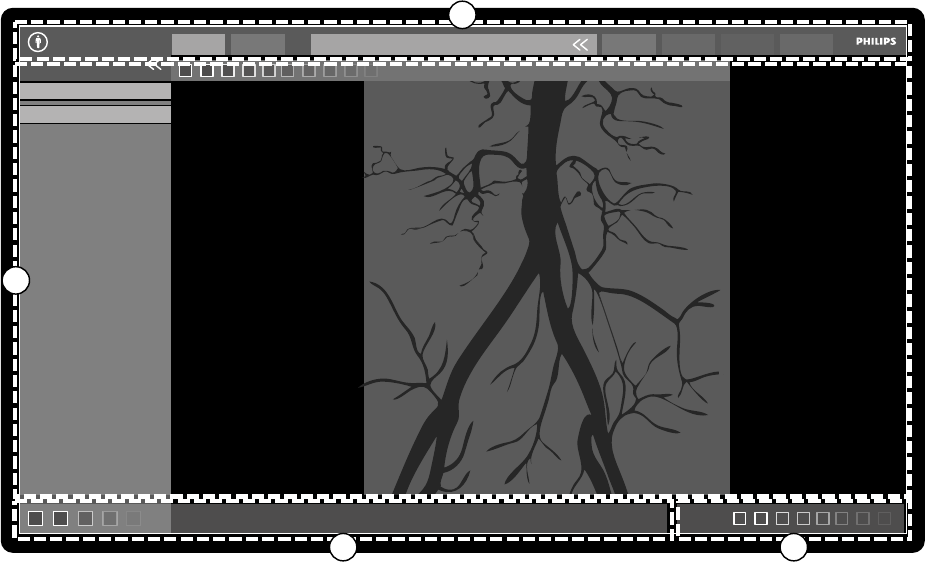

18.1.1 Monitor akwizycji.................................................................................................342

18.1.2 Monitor do przeglądania......................................................................................344

18.2 FlexSpot (opcja)....................................................................................................................346

18.2.1 Główny monitor FlexSpot.....................................................................................346

18.2.2 Dodatkowy monitor FlexSpot...............................................................................347

18.2.3 Dodatkowy system FlexSpot................................................................................ 347

18.3 FlexVision (opcja)................................................................................................................. 347